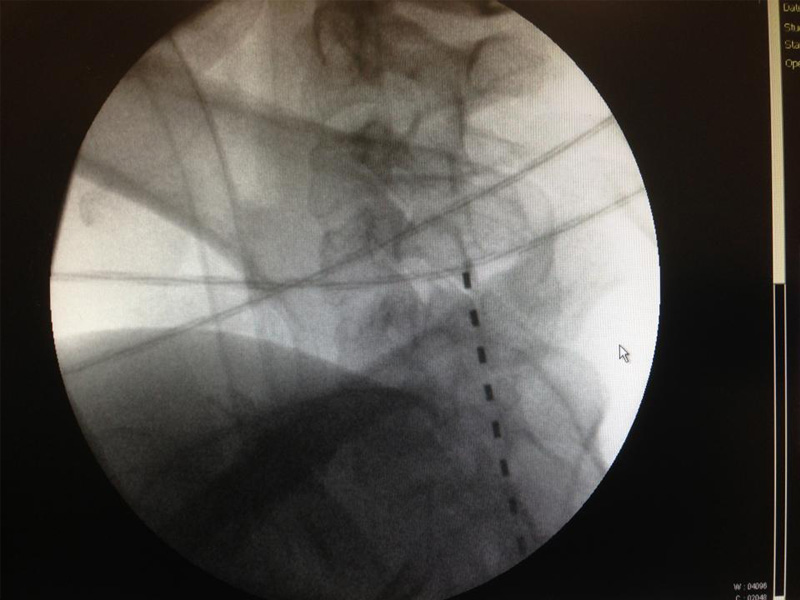

Segundo o anestesiologista, «após o diagnóstico temos várias possibilidades terapêuticas como a radiofrequência, ozonoterapia, nucleoplastia ,vertebroplastia, bloqueios de nervo periférico, epidurais ou a neurostimulação».

Radiofrequência, Ozonoterapia, Nucleoplastia, Vertebroplastia

Outra técnica também aplicada no tratamento da dor crónica é a Radiofrequência. Recomendada para artroses da coluna vertebral, síndrome golpe do coelho (quando as pessoas sofrem um acidente de automóvel ou outro que origina dores a nível do pescoço e membros superiores), instabilidade da coluna vertebral, dores pós cirúrgica da coluna ou hérnias discais.

«Após anestesia local o médico insere uma agulha com uma ponta especial que emite radiofrequência e faz com que os nervos deixem de enviar estímulos dolorosos para o cérebro», diz o especialista.

A Vertebroplastia está indicada para situações de colapso provocado por osteoporose, metástase óssea ou trauma.

Segundo Armando Barbosa, esta técnica «consiste na reconstrução de vértebras fracturadas na sequência de osteoporose, metástases de tumores noutras áreas do corpo ou traumatismos. Esta técnica, também percutânea permite estabilizar e fortalecer as vértebras lombares e torácicas».

A entrada da agulha é feita através da pele até penetrar na vértebra para fazer o preenchimento com um cimento especial para a fortalecer.